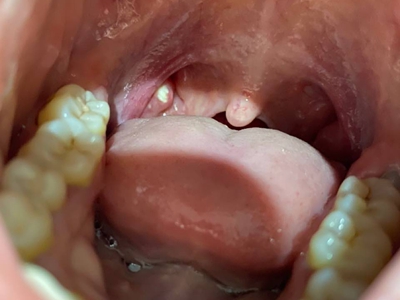

扁桃体结石是指发生在扁桃体隐窝的结石,是扁桃体隐窝细胞聚集所致的灰白色钙化团,扁桃体结石临床较少见。

扁桃体结石多呈灰白色,表面粗糙,质地坚硬。部分患者可自觉咽部有异物,结石较大者,进食可出现阻挡感。并发扁桃体炎症时,可出现患侧扁桃体肿大、咽痒、刺激性咳嗽等症状,甚则可出现咽喉肿痛、吞咽困难、发热等全身症状。

扁桃体内可发现灰白色、质地较硬的细小沙石,或可在肿大的扁桃体内触及较硬的肿块,触时有微痛感。